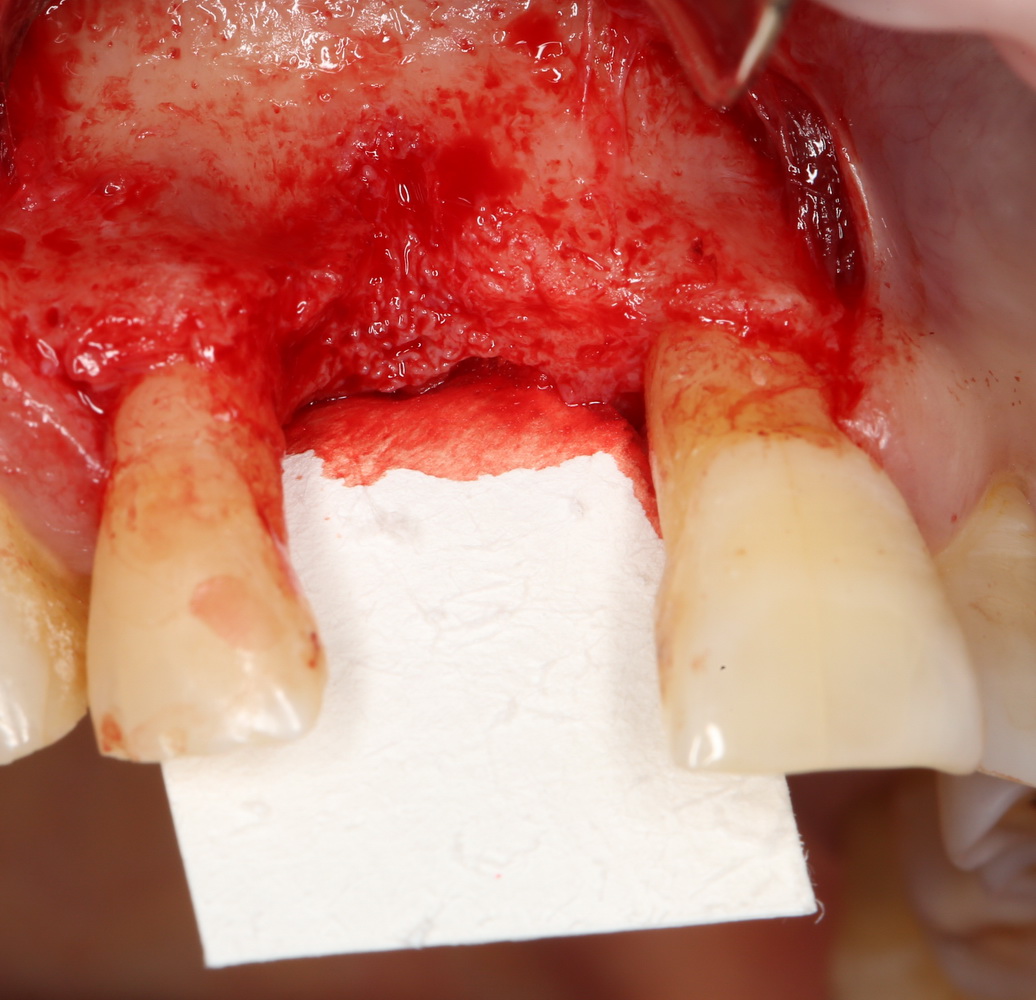

В этом случае остеопластика делается отдельной процедурой. Ее принципы точно те же, но уже без импланта. Например:

Имплантировать в таких условиях — заведомо обрекать себя на хреновый, с точки зрения эстетики и функциональности, результат. Поэтому первым этапом проводим остеопластику. Объем небольшой, использовать в таких объемах костный блок не очень рационально. Воспользуемся аутокостной стружкой и мембраной.

Сначала фиксируется BioGide. Это легко:

Затем укладывается и конфигурируется аутокостная стружка: